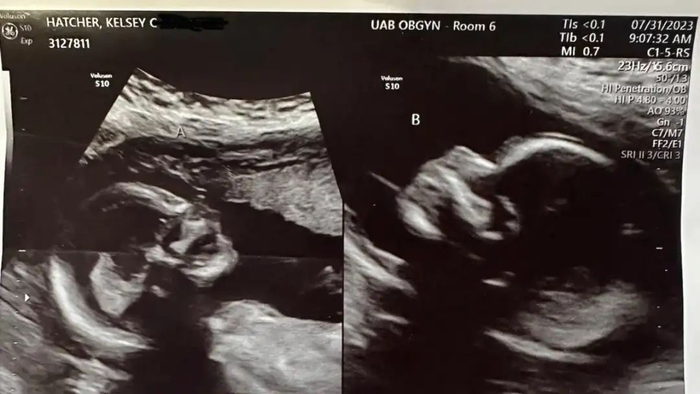

B超检查显示,凯尔西·哈彻的两个子宫同时妊娠。图源/IG

2023年7月31日的B超显示,两个胎儿发育正常。图源/Fox News